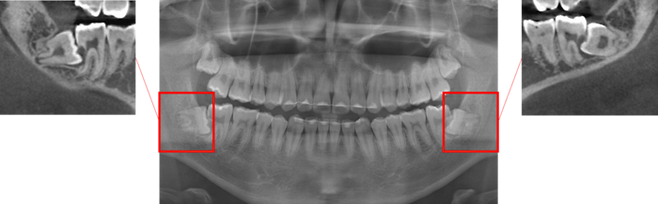

매복해 있다 통증을 유발하는 사랑니는 잇몸 부종과 염증을 유발하는 원인이 될 수 있으므로 주의가 필요하다. 전문가들은 사랑니가 인접한 치아를 손상시키거나 물혹·종양까지 발생하게 만들면 발치가 필요하다고 조언한다.

사랑니는 잇몸을 뚫고 나오는 방향이 비뚤어진 경우는 물론이고, 잇몸 안에 매복해 있을 때도 가까이 있는 치아의 우식(충치)을 일으키기 쉽다. 평소 증상이 없으면 존재 자체를 인지하지 못할 때가 많지만 비스듬하거나 수평인 방향으로 맹출하면 잇몸이 붓고 통증을 유발하는 치주염이나 치관주위염을 유발하기도 한다. 특히 치아머리 주변에 염증이 생기는 치관주위염은 심할 경우 입을 잘 벌리기 어려운 개구 장애까지 불러올 수 있다.

사랑니를 반드시 빼야 하는 상태로는 인접 치아가 손상되거나 그럴 가능성이 높을 때, 또는 치관주위염과 낭종(물혹), 종양이 발생한 경우가 대표적이다. 서미현 서울대치과병원 원스톱협진센터 교수(구강악안면외과 전문의)는 “발치 후 통증은 불가피하게 나타날 수 있으며, 증상의 정도는 보통 발치 당일 가장 심할 수 있다”며 “발치 후 마취가 풀리기 전에 처방받은 약을 복용하되, 그래도 통증이 심하다면 담당 치과의사와 상의해 추가적인 진통소염제 복용을 고려할 수 있다”고 말했다.

특히 낭종·종양과 관련될 수 있는 매복된 사랑니는 겉으로 드러나는 증상이 잘 발견되지 않더라도 예방적인 차원에서 제거할지를 판단할 때도 있다. 서 교수는 “사랑니는 비정상적인 맹출로 관리가 어렵고, 실제 기능을 하지 않는 경우가 많아 인접 치아의 관리를 위해 발치가 필요한 경우가 많다”며 “사랑니로 인한 증상과 통증이 없다고 해서 문제가 없는 것이 아니므로 구강악안면외과 전문의와 상담하거나 주기적인 검진이 꼭 필요하다”고 말했다.